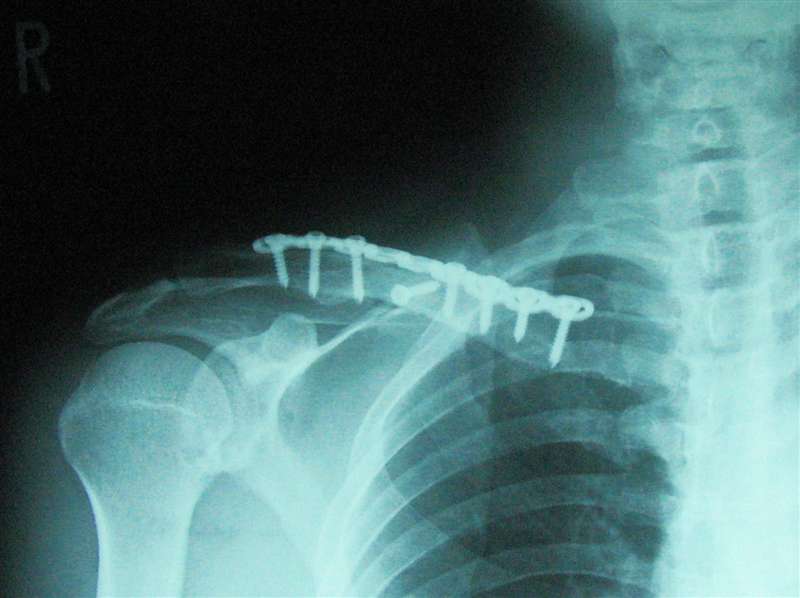

少し前に執刀した先生からボルトというかビスみたいな小さなネジ7本とプレートで骨を固定し

無事終了したという説明を受けたと聞かされました。(予定よりネジ2本多かったです)

※後日さらにもう1本多い8本だった事が判明しました。

※後の4月の検診の時のレントゲン写真です。